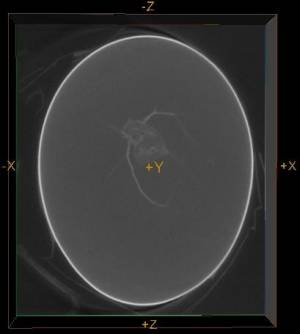

Figure 4. Transverse CT image of mouse